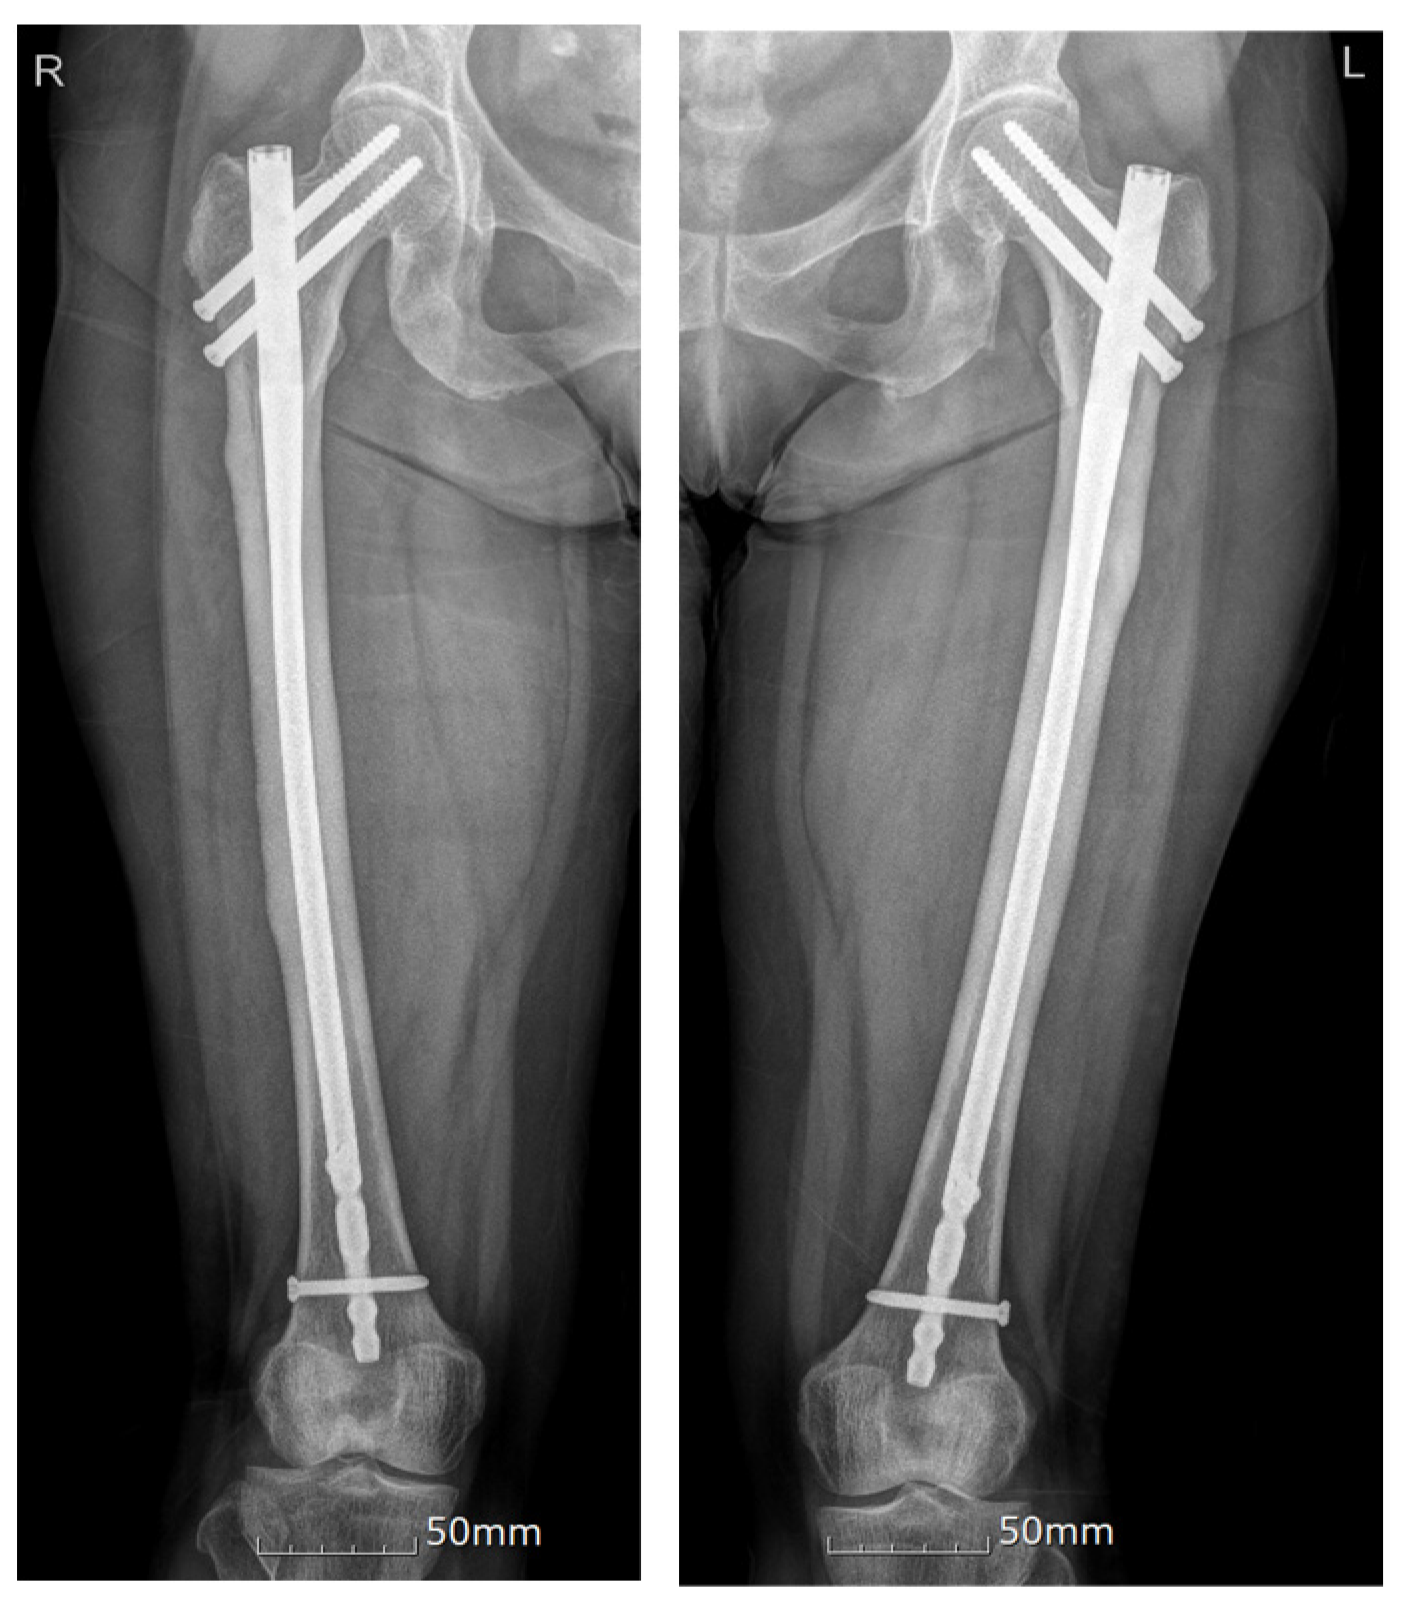

| 1 | Our case | F, 64 | O/O | Simultaneous | Ibandronate 150 mg monthly for 10 years | Prox/prox | PIM nailing/PIM nailing | Teriparatide | NA |